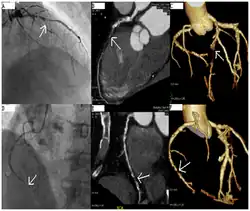

A coronary catheterization is a minimally invasive procedure to access the coronary circulation and blood filled chambers of the heart using a catheter. It is performed for both diagnostic and interventional (treatment) purposes.

Coronary catheterization is one of the several cardiology diagnostic tests and procedures. Specifically, through the injection of a liquid radiocontrast agent and illumination with X-rays,[1] angiocardiography allows the recognition of occlusion, stenosis, restenosis, thrombosis or aneurysmal enlargement of the coronary artery lumens; heart chamber size; heart muscle contraction performance; and some aspects of heart valve function. Important internal heart and lung blood pressures, not measurable from outside the body, can be accurately measured during the test. The relevant problems that the test deals with most commonly occur as a result of advanced atherosclerosis – atheroma activity within the wall of the coronary arteries. Less frequently, valvular, heart muscle, or arrhythmia issues are the primary focus of the test.

CT angiography can act as a less invasive alternative to Catheter angiography. Instead of a catheter being inserted into a vein or artery, CT angiography involves only the injection of a CT-visible dye into the arm or hand via an IV line. CT angiography lowers the risk of arterial perforation and catheter site infection. It provides 3D images that can be studied on computer, and also allows measurement of heart ventricle size. Infarct area and arterial calcium can also be observed (however those require a somewhat higher radiation exposure). That said, one advantage retained by Catheter angiography is the ability of the physician to perform procedure such as balloon angioplasty or insertion of a stent to improve blood flow to the artery.[8]